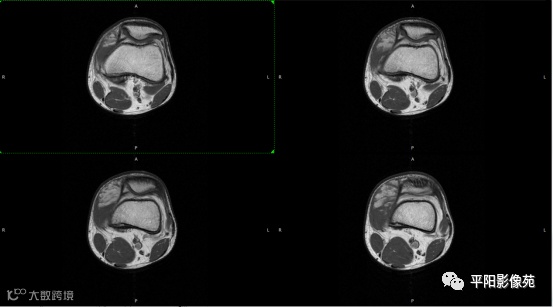

影像表现:

左膝关节股内侧肌内见多房样短T1长T2信号,内可见分隔,增强扫描明显强化,分隔未见明显强化,病灶局部与股骨远端分界不清。

MRI表现:好发于下肢, 较大病灶多为与肢体长轴一致的梭形, 边缘不清, 较小病灶呈类圆形, 边缘较清;②T1WI呈等或稍高信号, 病灶内部或边缘可见线条状或花边状高信号灶, 类似于皮下脂肪信号, T2WI上为明显高信号, 为本病特征性MRI表现;③病灶内静脉石及血管流空影为又一特征MRI表现;④GD-DTPA增强, 病灶明显强化, 其内低信号间隔无强化;⑤可见骨外形改变, 骨质增生及骨质吸收等表现。